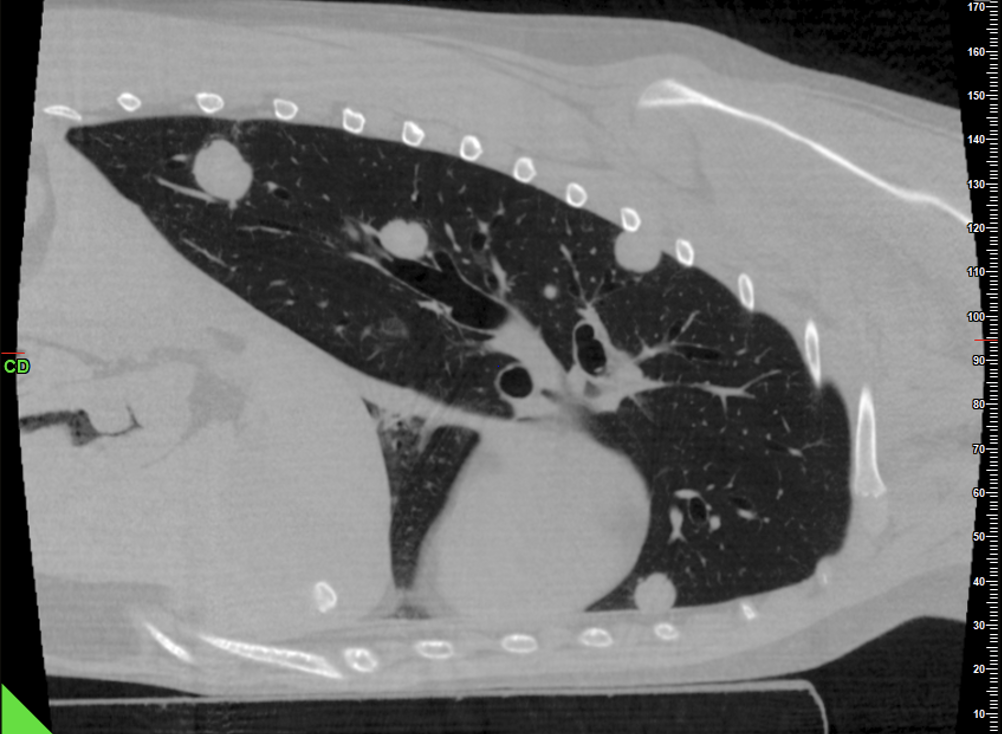

Thorax: Im Thorax wird das CBCT ebenso routinemäßig eingesetzt. Es erlaubt die Beurteilung von Raumforderungen, größeren parenchymatösen Veränderungen und mediastinalen Prozessen bei vergleichsweise kurzer Untersuchungszeit (Abb. 3 & 4).